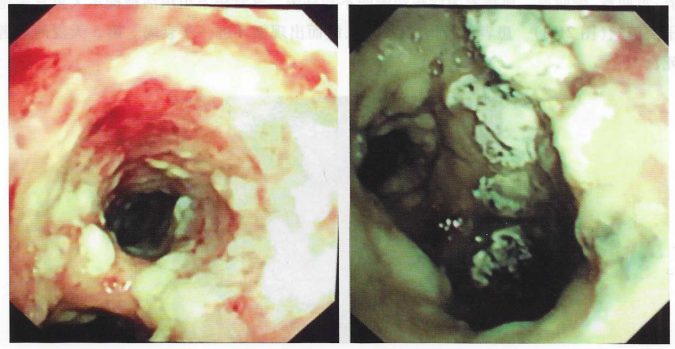

床旁支气管镜检查示:双肺各叶段支气管黏膜充血水肿,管壁多发白色膜状赘生物,触之易出血,管腔明显狭窄(图2)。予伏立康200 mg q12h+两性霉素B 10 mg qd+头孢哌酮舒巴坦3.0 g q12h抗感染,同时予补液、呼吸支持、控制血糖、营养支持等治疗。

图2  入院时气管镜检查

入院第5天,化验回报血GM试验11.05 pg/ml,BALF GM试验10.70 pg/ml。BALF培养:黄曲霉、烟曲霉。血培养为泛耐药鲍曼不动杆菌。气管镜下组织活检提示大量真菌孢子及菌丝(图3)。患者氧合仍难以维持,继而出现循环进一步衰竭。第5天夜间患者死亡。

图3  气管镜下组织活检提示大量真菌孢子及菌丝